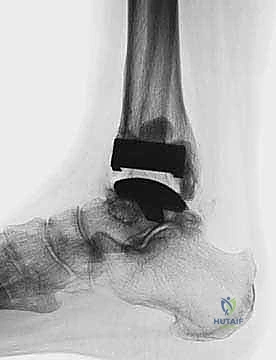

TECH FIG 5 • Subtalar arthrodesis. A. Postoperative AP view with subtalar arthrodesis using a single OA cancellous screw.

TECH FIG 5 • Subtalar arthrodesis. B. Lateral view.

FIG 6 • The TNK ankle replacement for rheumatoid arthritis of the ankle (cemented replacement). A. Preoperative AP view. B. Preoperative lateral view. C. Postoperative AP view 2 years 6 months after the surgery. D. Postoperative lateral view.